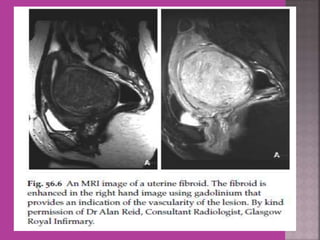

 Myoma—to differentiate myoma from

adenomyoma.localization of myoma—sub

serous/ intra mural or sub mucous.

Degeneration Of Fibroid

Cystic Degeneration of

Fibroid